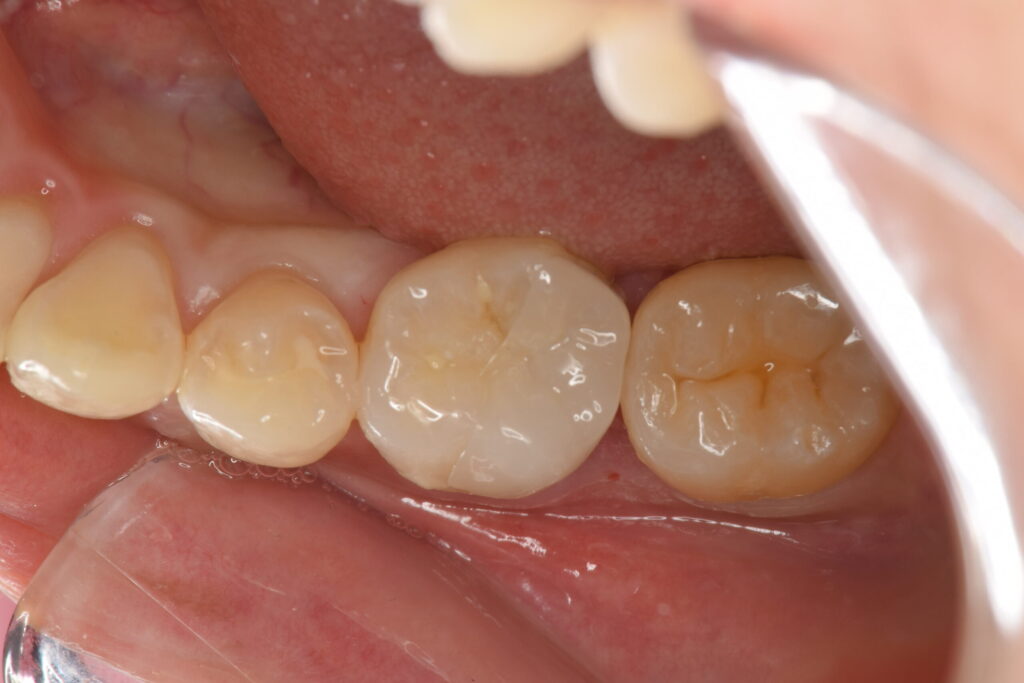

ラバーダム防湿下でセラミックオーバーレイ(テーブルトップベニヤ)を接着しました。

白丸の範囲、隙間が全くないことがわかります。

隙間を作らないことで汚れや細菌が入るスペースを与えず、虫歯の再発予防に寄与すると考えられます。